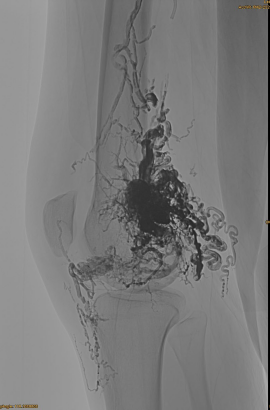

Informasi Dasar Pasien: Wanita, 36 tahun; AVM Pelvis, pinggul, lutut, OSG kiri, beberapa pre - embolisasi.

Produk yang digunakan: 3pcs LAVA-34,14pcs LAVA-18.

DSA Awal:

Hasil Akhir:

Fase akhir, EMBO lain yang diperlukan, tetapi jauh lebih baik: